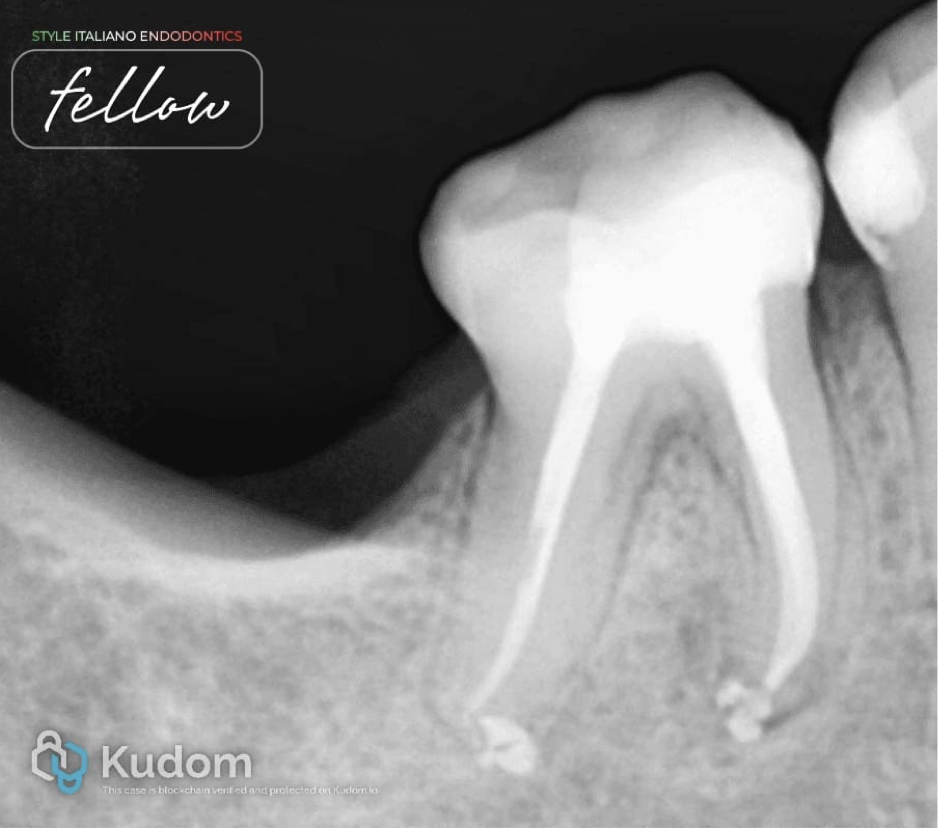

Fig. 2

After rubber dam isolation, caries was removed and deroofing was done. Initial scouting was done with 10 number K-files, and working length was measured. Protaper Gold rotary files were used to enlarge the canal space for better irrigant exchange. The mesial system was prepared till the F1file, and the distal system was prepared till the F2 file in a crown-down manner. Recapitulation was done after every rotary file and in the presence of sodium hypochlorite. Irrigation activation was done with air sonic device. EDTA liquid was use before the final rinsing with sodium hypochlorite.

Fig. 3

After irrigation and activation of irrigants, canals were found dry. Non-standardised medium-sized gutta percha cones were checked as master cones.